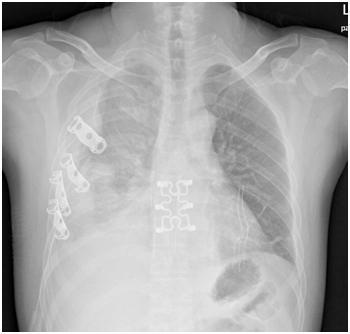

▲术后复查胸片 。

来自龙岗的李先生(化名)就是这一创新术式的受益者之一 , 今年1月 , 40岁李先生因为车祸受伤住进了龙岗中心医院胸外科 , 入院时伤情较重 , 相关检查提示双侧多发肋骨骨折 , 胸骨骨折 , 双肺挫伤 , 右侧血气胸 。 洪琼川主任团队迅速制定救治方案 , 经术前讨论后决定为李先生施行“胸腔镜下右侧肋骨骨折内固定、胸骨骨折内固定术” 。 由于患者右侧第3-6肋骨错位明显 , 术中给予记忆合金肋骨接骨板固定了错位肋骨 , 胸骨爪固定胸骨骨折处 。 手术过程顺利 , 术后经过抗感染活血促骨折愈合雾化排痰等治疗 , 复查胸部X线提示肋骨爪及胸骨爪固定良好 , 李先生住院一周后顺利康复出院 。